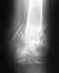

здравствуйте.несколько дней назад при падении получил закрытый перелом правой голени со смещением.

сделали снимок,наложили гипс.на приеме врач поглядев описание отправил домой.я решил подстраховаться и отправился в республиканскую поликлинику.врач направил меня в платную поликлинику где сам так же работает.на основании тех же описаний рентгеновских снимков он предложил мне операцию-платную.подскажите пожалуйста не кажутся ли такие действия вам подозрительными и стоит ли соглашаться на возможно псевдооперацию с целью получения им прибыли из воздуха.Спасибо.